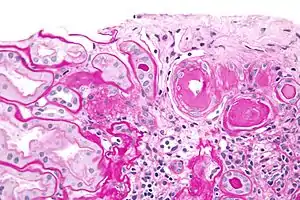

| Micrograph showing renal arterial hyalinosis – pink ring right-of-centre. PAS stain. | |

In the kidneys, as a result of benign arterial hypertension, hyaline (pink, amorphous, homogeneous material) accumulates in the walls of small arteries and arterioles, producing the thickening of their walls and the narrowing of the arterial openings, a process known as arteriolosclerosis. The resulting inadequate blood flow produces tubular atrophy, interstitial fibrosis, and glomerular alterations (smaller glomeruli with different degrees of hyalinization – from mild to sclerosis of glomeruli) and scarring around the glomeruli (periglomerular fibrosis). In advanced stages, kidney failure will occur. Functional nephrons[6] have dilated tubules, often with hyaline casts in the opening of the tubules. Additional complications often associated with hypertensive nephropathy include glomerular damage resulting in protein and blood in the urine.

In benign nephrosclerosis, the changes occurring are gradual and progressive, however, there can be sufficient kidney reserve capacity to maintain adequate kidney function for many years.[10] The large renal arteries exhibit intimal thickening, medial hypertrophy, duplication of the elastic layer. The changes in small arterioles include hyaline arteriolosclerosis (deposition of hyaline, collagenous material), which causes glomerular collapse (wrinkling and thickening of capillary basement membranes and collapse of capillary lumen) and solidification (glomeruli exhibit sclerosis and increase in mesangial matrix). The degree of scarring correlates with the degree of glomerular filtration deficit.

Light micrograph showing hypertensive glomerular lesion of hypertensive nephropathy: global glomerular collapse and filling of Bowman's space with a lightly staining collagenous material.

Light micrograph showing hypertensive glomerular lesion of hypertensive nephropathy: global glomerular collapse and filling of Bowman's space with a lightly staining collagenous material. Light micrograph of glomerulus showing secondary segmental sclerosis of hypertensive nephropathy.